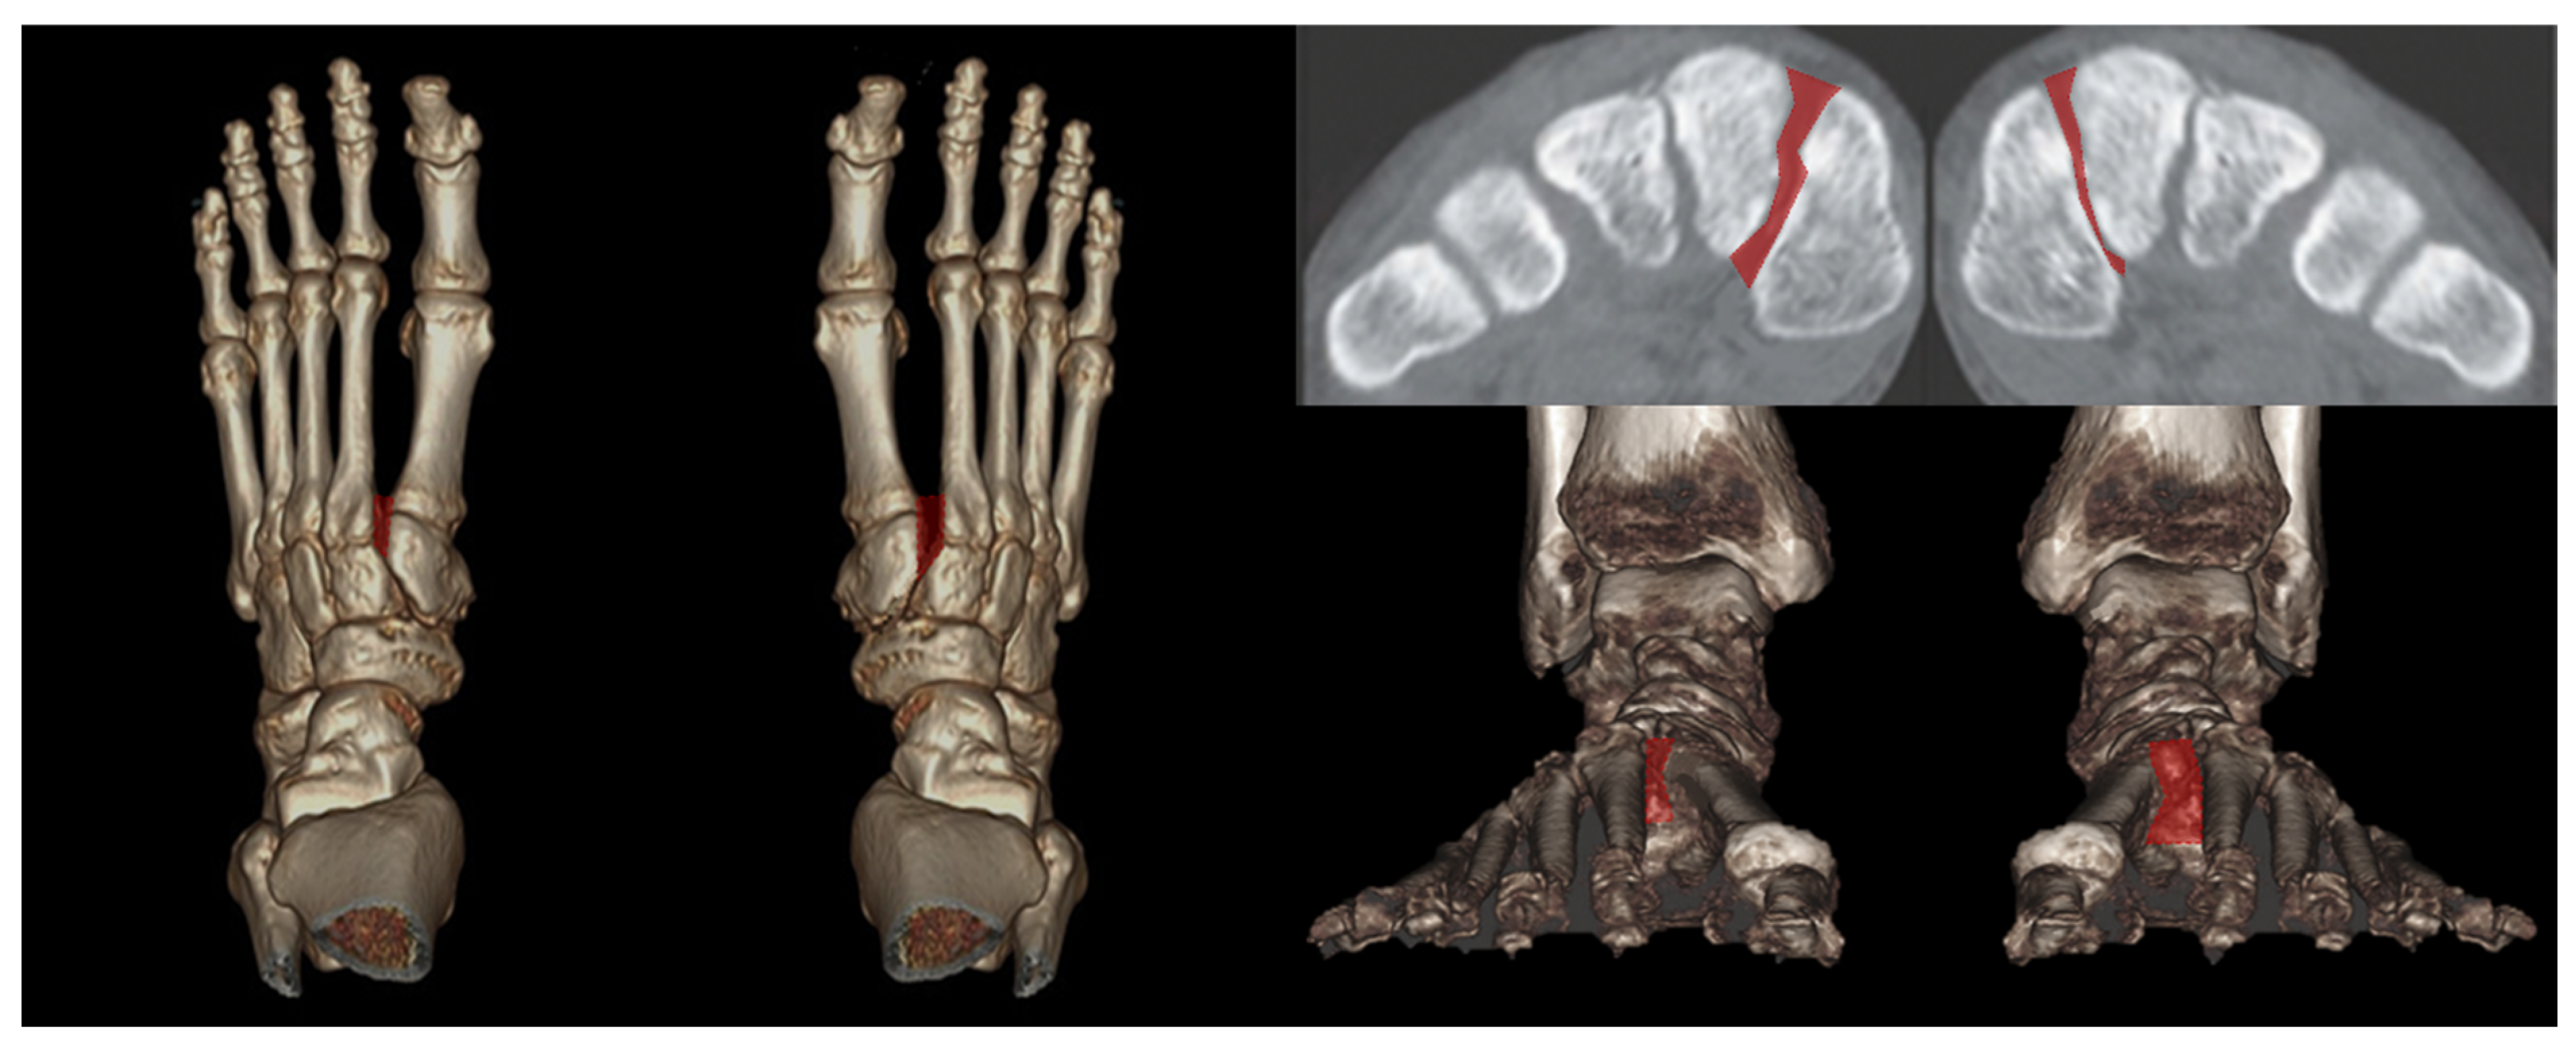

Instead of conventional axial measurement of the Lisfranc joint, some novel WBCT parameters have been developed and introduced to be used in the clinical setting. Sripanich evaluated 96 cadaveric specimen and designed a WBCT protocol to enhance the reliability of Lisfranc joint measurement [27]. They found that measuring the distance between medial cuneiform and second metatarsal with coronal WBCT imaging would be a reproducible way to localize the interosseous Lisfranc ligament injury. Similarly, Bhimani et al evaluated the Lisfranc joint complex using one dimensional (1D), two dimensional (2D), and 3D measurements on WBCT scans among operatively confirmed Lisfranc instability (Figure 5) [28]. They concluded that coronal 3D volumetric measurement had higher sensitivity and specificity than 2D and 1D measurements, because the second metatarsal tends to displace both laterally and superiorly in Lisfranc injury. Despite its inherent limitation to be actively used in acute condition, WBCT may enhance diagnostic accuracy for suspicious Lisfranc injuries with uncertain conventional radiograph findings.

Figure 5. 3D volumetric measurement of the Lisfranc joint.